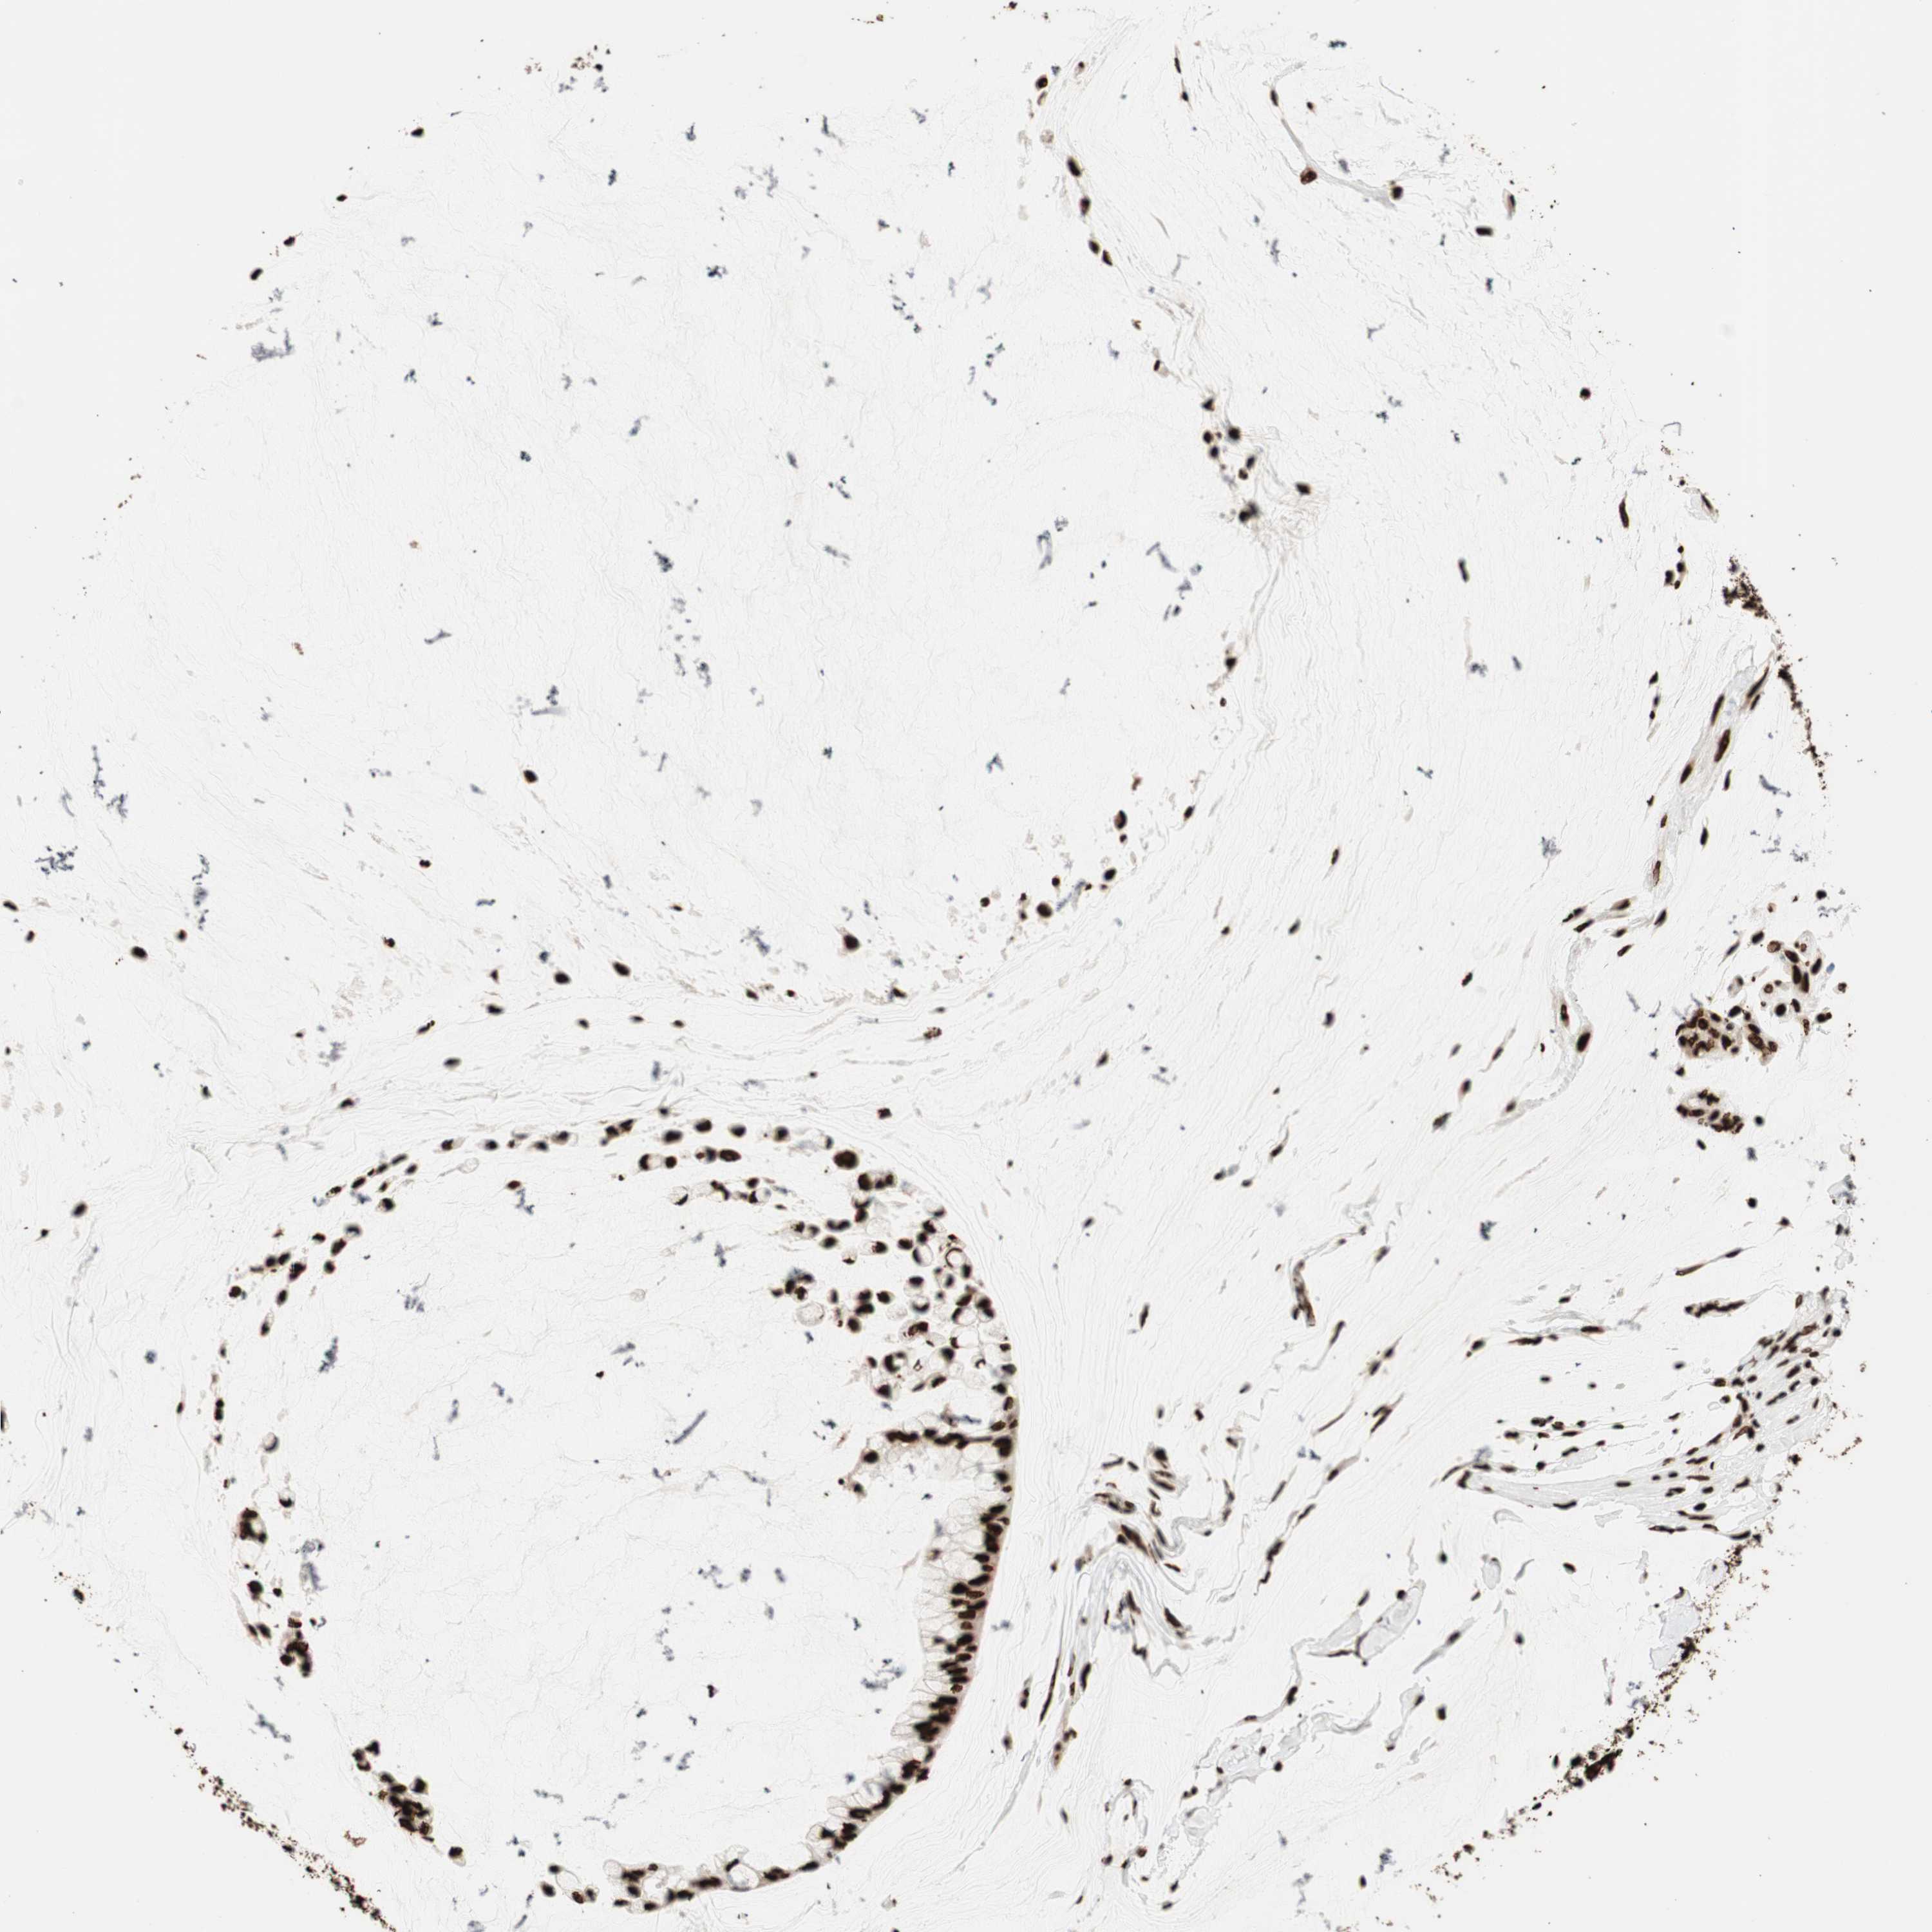

OVARIAN CANCER - Protein expressioni

A mouse-over function shows sample information and annotation data. Click on an image to view it in a full screen mode. Samples can be filtered based on level of antibody staining by selecting one or several of the following categories: high, medium, low and not detected. The assay and annotation is described here.

Note that samples used for immunohistochemistry by the Human Protein Atlas do not correspond to samples in the TCGA dataset.

Antibody stainingi

Antibody staining in the annotated cell types in the current human tissue is reported as not detected, low, medium, or high, based on conventional immunohistochemistry profiling in selected tissues. This score is based on the combination of the staining intensity and fraction of stained cells.

Each image is clickable and will lead to virtual microscopy that enables deeper exploration of all samples and also displays staining intensity scores, fraction scores and subcellular localization as well as patient and tissue information for each sample.

Antibody CAB008558

Staining

High

Medium

Low

Not detected

Intensity

Strong

Moderate

Weak

Negative

Quantity

>75%

75%-25%

<25%

None

Location

Nuclear

Cytoplasmic/membranous

Cytoplasmic/membranous,nuclear

Cystadenocarcinoma, serous, NOS

Carcinoma, endometroid

Cystadenocarcinoma, mucinous, NOS

Carcinoma, NOS